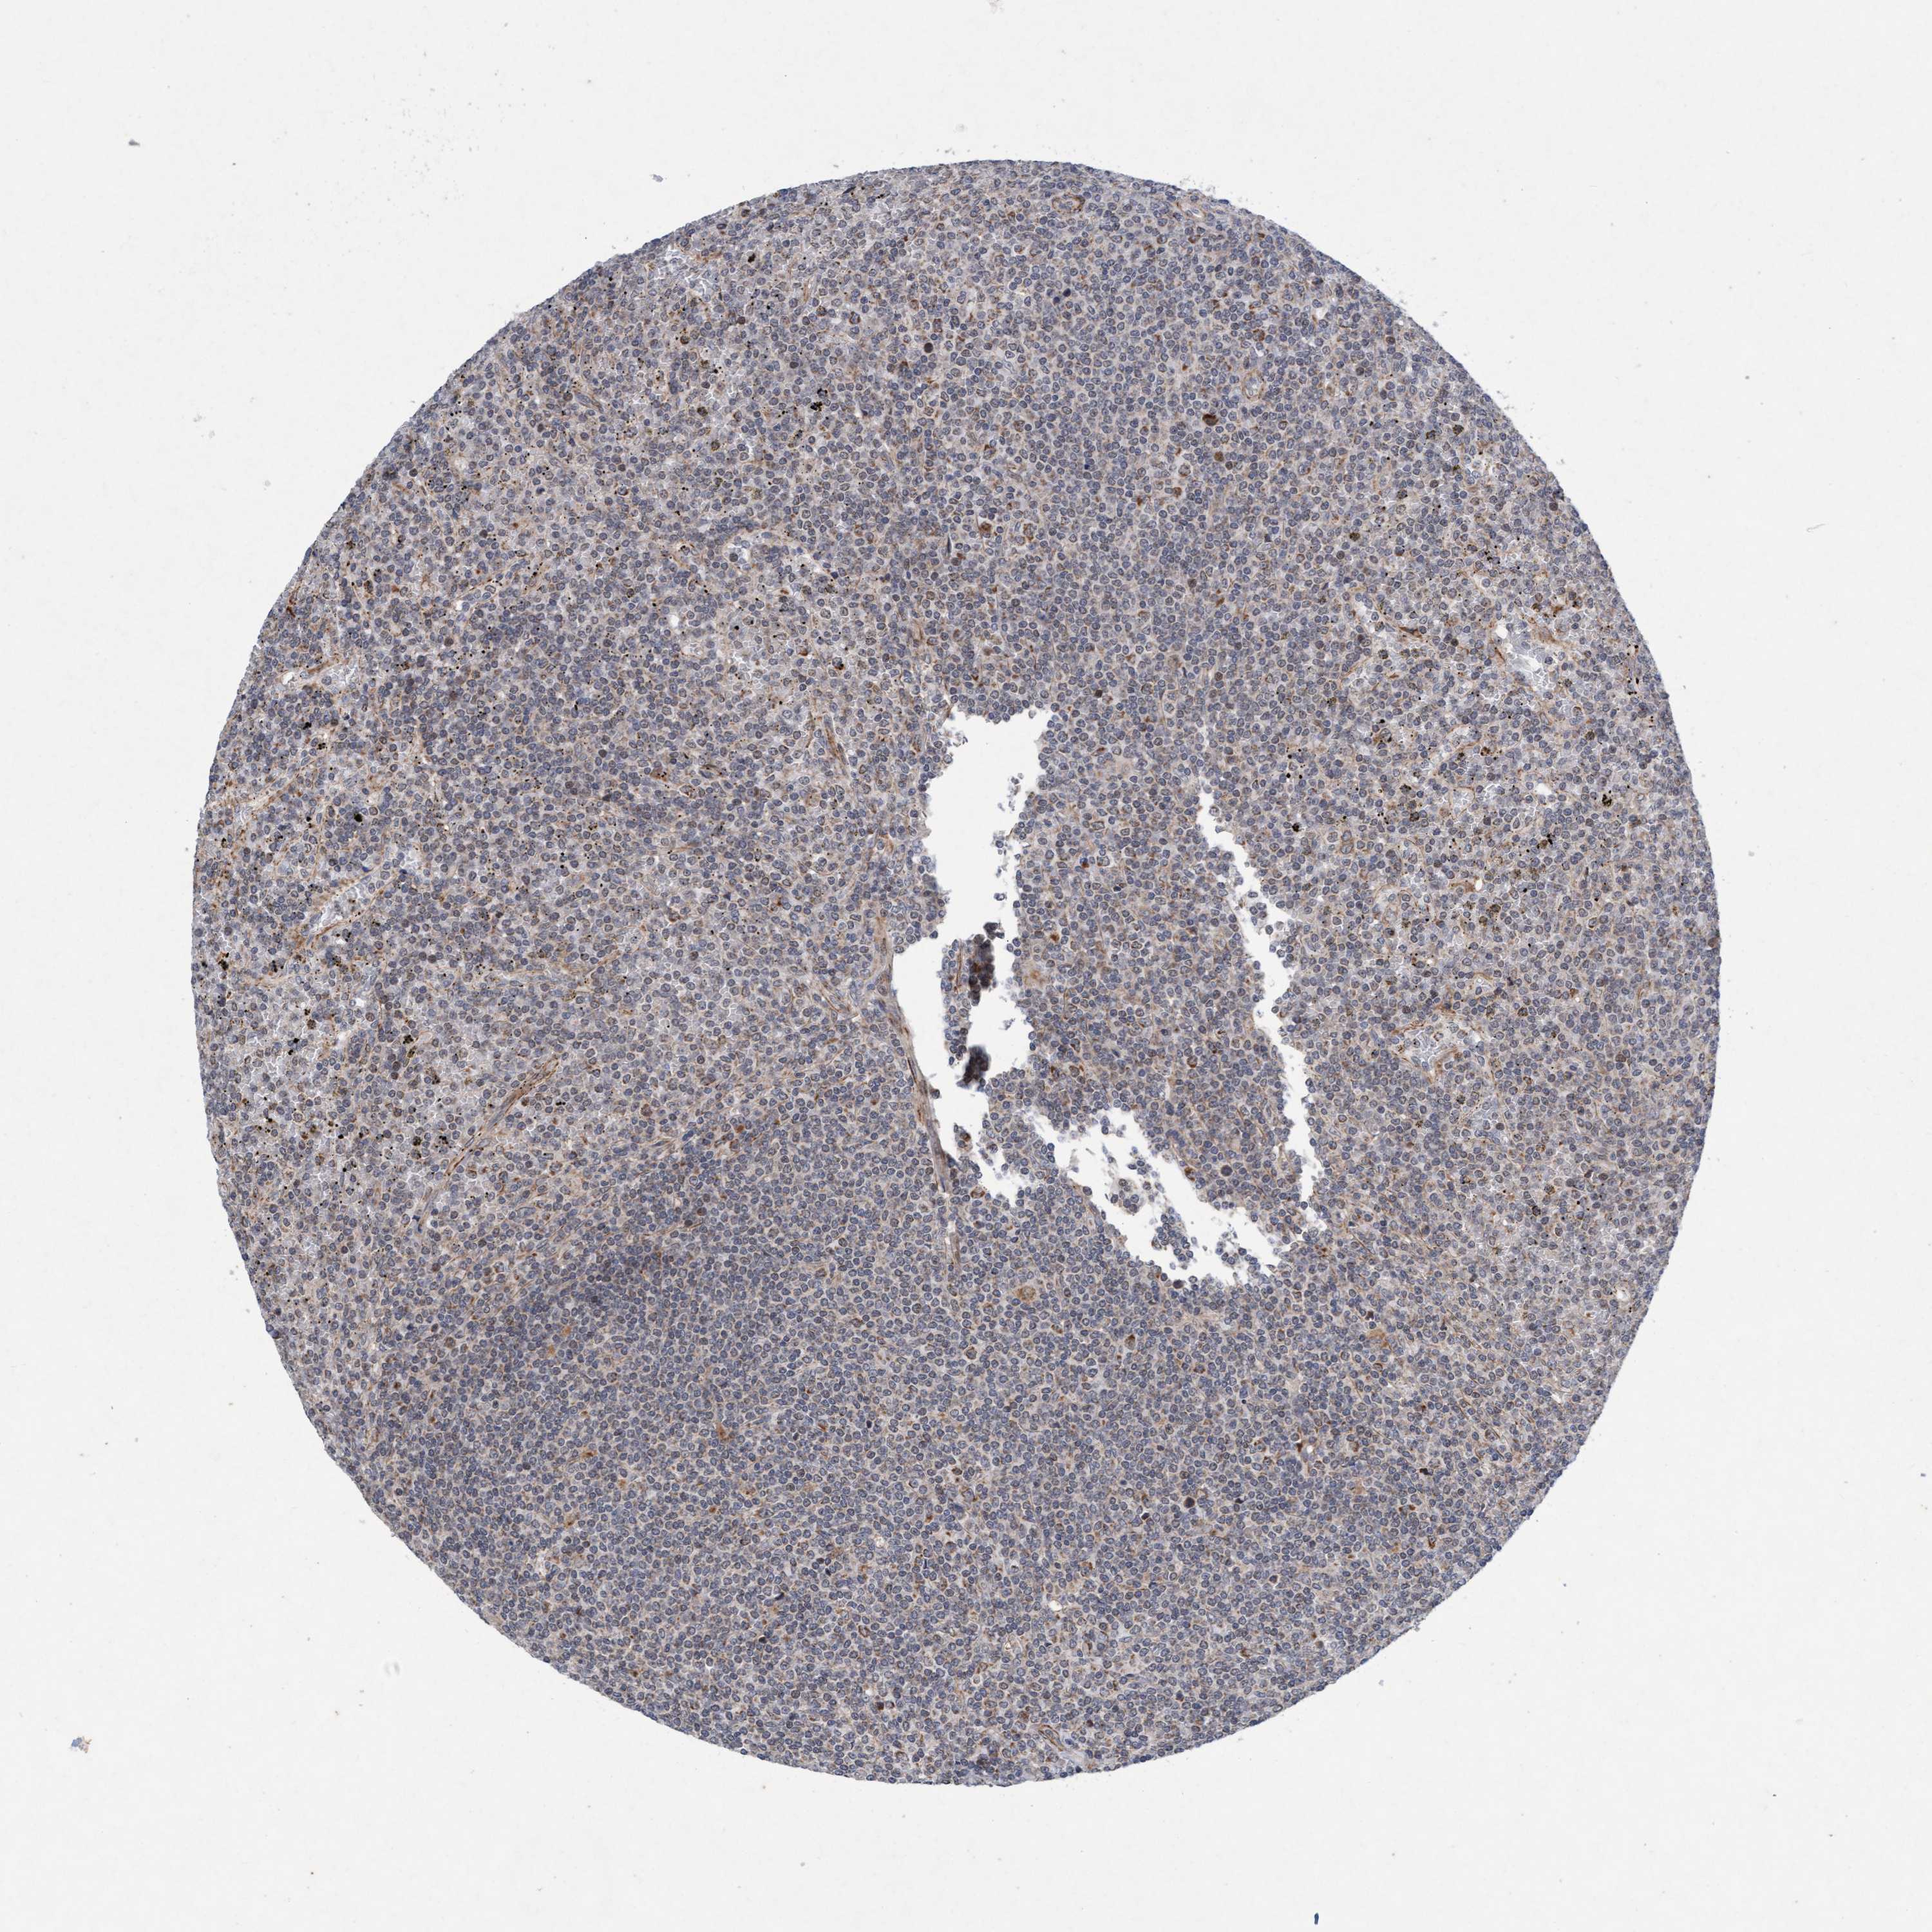

LYMPHOMA - Protein expressioni

A mouse-over function shows sample information and annotation data. Click on an image to view it in a full screen mode. Samples can be filtered based on level of antibody staining by selecting one or several of the following categories: high, medium, low and not detected. The assay and annotation is described here.

Each image is clickable and will lead to virtual microscopy that enables deeper exploration of all samples and also displays staining intensity scores, fraction scores and subcellular localization as well as patient and tissue information for each sample.

Antibody HPA023187

Antibody CAB034226

Staining

High

Medium

Low

Not detected

Intensity

Strong

Moderate

Weak

Negative

Quantity

>75%

75%-25%

<25%

None

Location

Nuclear

Cytoplasmic/membranous

Cytoplasmic/membranous,nuclear

Hodgkin's disease, NOS

Malignant lymphoma, non-Hodgkin's type, High grade

Malignant lymphoma, non-Hodgkin's type, Low grade